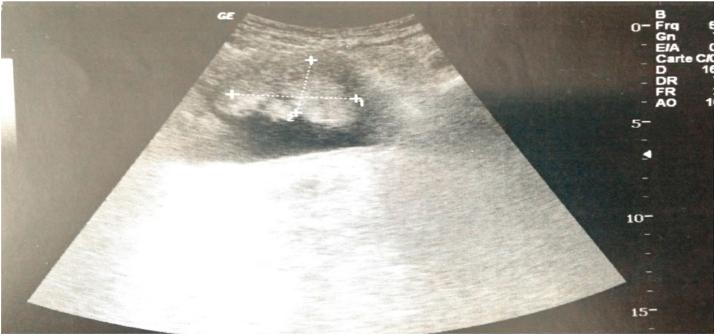

PRESENTATION OF CASE

We report the case of a 50-year-old patient with no pathological history who consulted for an episode of intermittent urinary mucosal secretion aggravated by the appearance of macroscopic hematuria. Without other associated clinical signs. Imaging examinations revealed a mass at the expense of the upper wall of the bladder. The cystoscopy allowed us to visualize the mass and the biopsy. Histological study revealed an adenocarcinoma of urachus. The patient underwent surgical exeresis and adjuvant chemotherapy. The evolution was marked by a deterioration of the general condition despite adequate management.

我们报告一例50岁无病史患者,因间歇性尿道黏膜分泌物增多并出现肉眼血尿前来就诊,无其他相关临床症状。影像学检查显示膀胱上壁有一肿块。膀胱镜检查使我们能够看到肿块并进行活检。组织学研究显示为脐尿管腺癌。患者接受了手术切除及辅助化疗。尽管治疗得当,但患者的总体状况仍逐渐恶化。